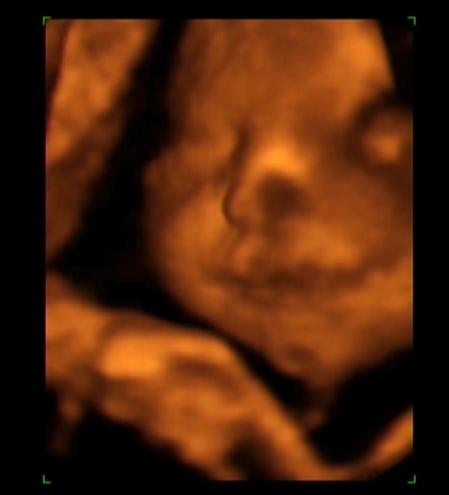

Na jelentem itt vagyok. Szóval minden oké, súlya 2100 gr, BPD: 85mm, TAD:77mm. A lényeg az, hogy a mellkasa keskenyebb az adott fejmérethez, ami nem gond még egyelőre, a dyaphilint azért írta, hogy ha legközelebb megyek akkor már ne legyen különbség. Elvileg ez segíti a jobb véráramlást és így szed még magára. Hosszt nem mondott csak annyit, hogy hosszú baba, de szeintem látszik a képeken is, hogy nincs összeszakadva annyira!!!!!! Megkönnyebbülés az van, dvd nézés egyfolytában.

Gyabi: nagyon szép pofikája van a Beninek!!! Meg a pocid és nagyon kerek :lol: